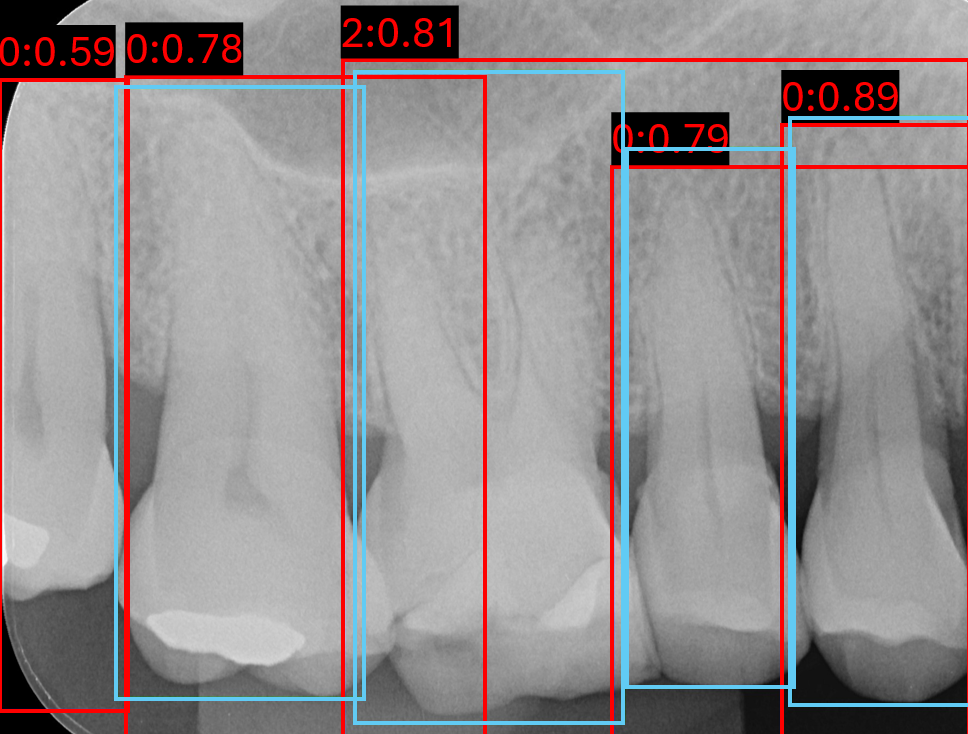

3.2.2 Keypoint Detection Results

Keypoint localisation was evaluated using PRCKPRCK across multiple thresholds, with and without post-processing in Table 5. At the coarse threshold PRCK0.5PRCK^{0.5}, YOLOv8 outperforms all other models, achieving 0.9120.912(±0.026\pm 0.026) on the validation set and 0.9000.900(±0.029\pm 0.029) on the external set, reflecting strong robustness against localisation error. In contrast, performance at the strict threshold PRCK0.05 indicates HRNet’s advantage in fine-grained precision compared to its lower generalised precision at lower thresholds, where it achieved the highest scores of 0.3750.375(±0.027\pm 0.027) on the validation set and 0.4050.405(±0.029\pm 0.029) on the external set.

Post-processing consistently improved strict-threshold PRCK0.05PRCK^{0.05} performance across models. For example, YOLOv8 increased from 0.3680.368(±0.059\pm 0.059) to 0.4040.404(±0.048\pm 0.048) on the validation set and from 0.3090.309(±0.083\pm 0.083) to 0.3560.356(±0.086\pm 0.086) on the external set. However, these gains in fine localisation were often accompanied by reductions at broader thresholds, PRCK0.25PRCK^{0.25} and PRCK0.5PRCK^{0.5}.

Analysing the validation set, in Figure 8, qualitatively shows that raw predictions rarely coincide with anatomically correct locations, often being detected within the tooth interior or entirely outside its boundary. Post-processing substantially improves localisation in most cases, shifting keypoints towards plausible mesial and distal edges, as shown in Figure 8(a) and 8(d). However, this refinement is heavily dependent on the quality of the raw detections. When predictions are excessively noisy, post-processing can amplify errors, relocating keypoints to implausible locations such as the crown or furcation apex, as seen in Figure 8(g) and Figure 8(h). This further explains the observed quantitative increase for prck0.05prck^{0.05}, but declination at more lenient thresholds, since small adjustments improve low-tolerance metrics, yet fail to increase high-tolerance thresholds.

Refer to caption

(a) Image 120 DeepPose

(b) Image 120 HRNet

(c) Image 120 RTMPose

(d) Image 120 YOLOv8

(e) Image 171 DeepPose

(f) Image 171 HRNet

(g) Image 171 RTMPose

(h) Image 171 YOLOv8

Figure 8: Six validation images with overlay keypoint results, where red points are the raw keypoint predictions and green points are the post-processed keypoints.

Further analysis of post-processing PRCKPRCK metrics at a range of thresholds in Figure 9, all models except HRNet show slightly reduced 0.50.5-0.20.2 threshold performance for post-processed keypoints compared to no post-processing. However, post-processed and non-post-processed performance inverts between a threshold of 0.20.2-0.10.1.